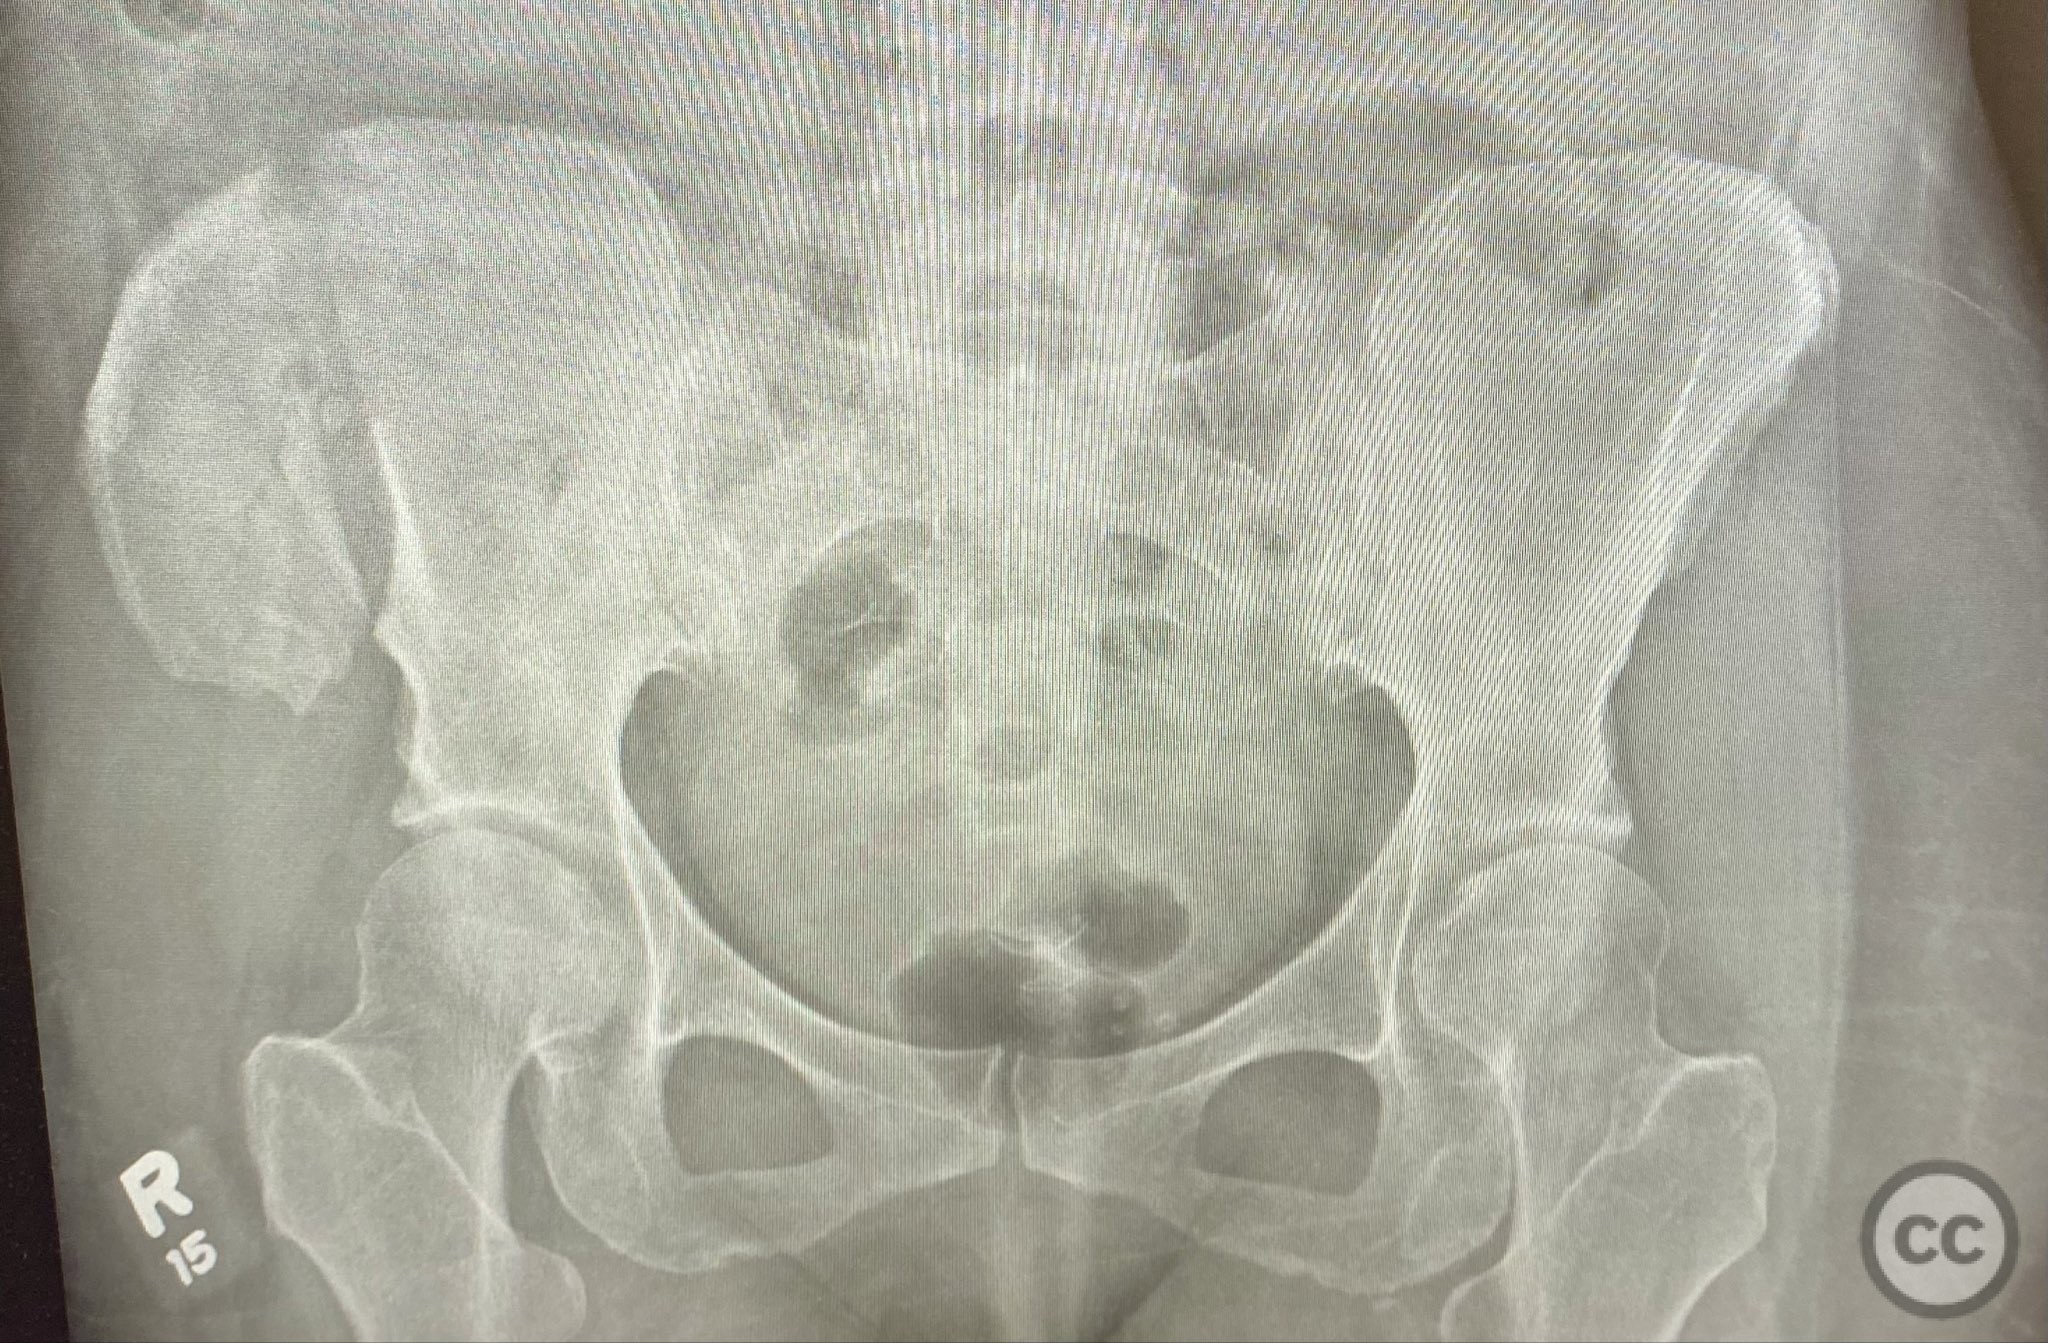

Pelvis - AO/OTA 6x